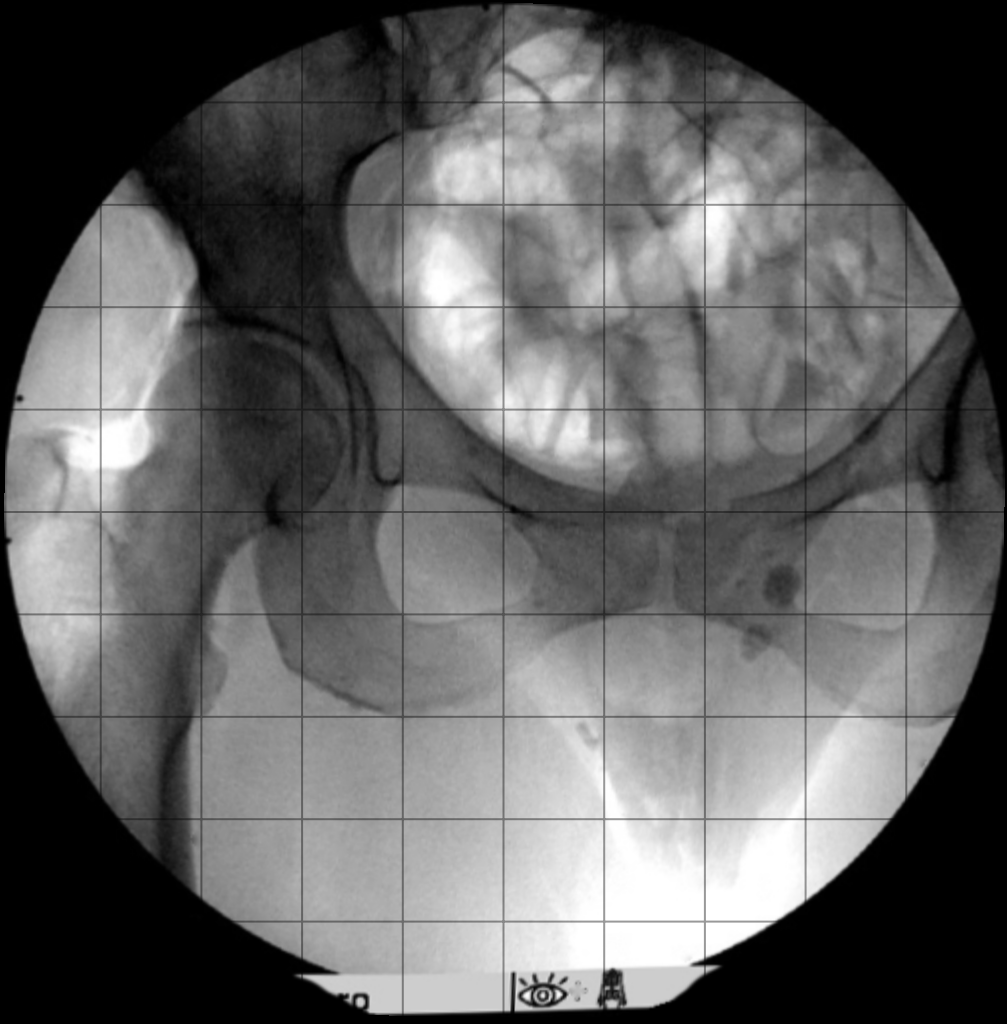

Distortion Simulator

Distortion: Grid:

Displaying Image 1 of 10